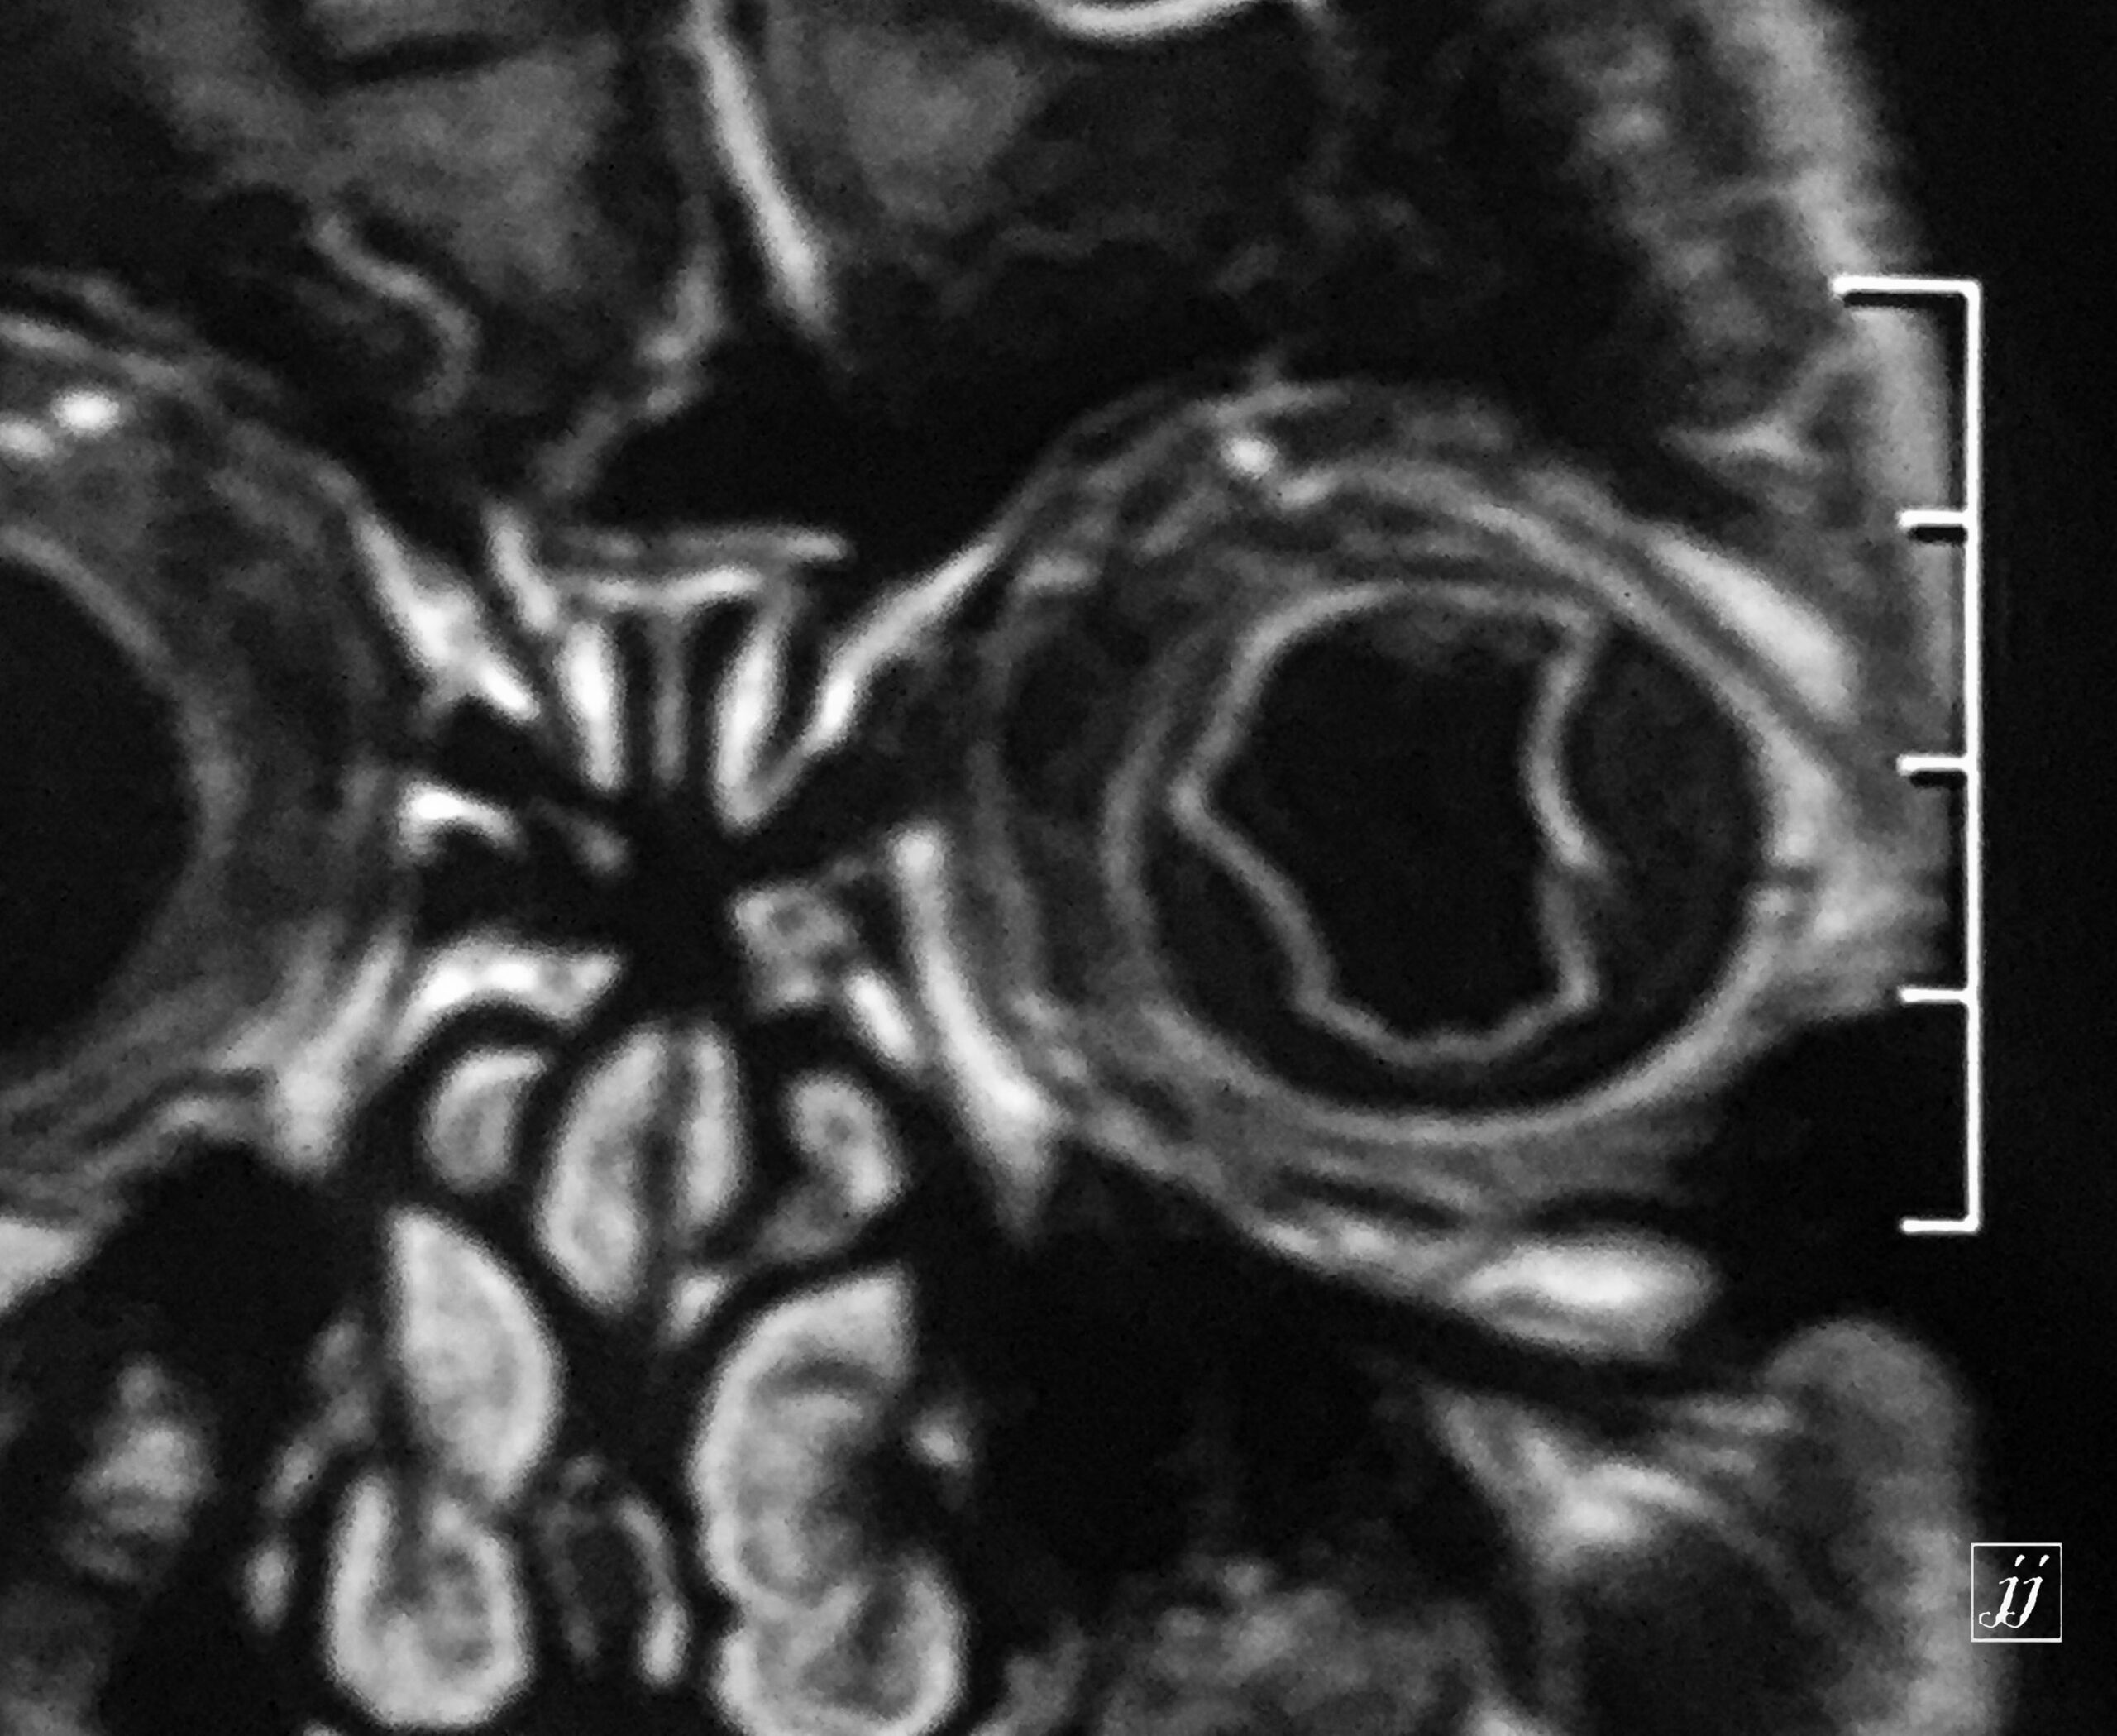

Orbit- vitreous detachment (7)